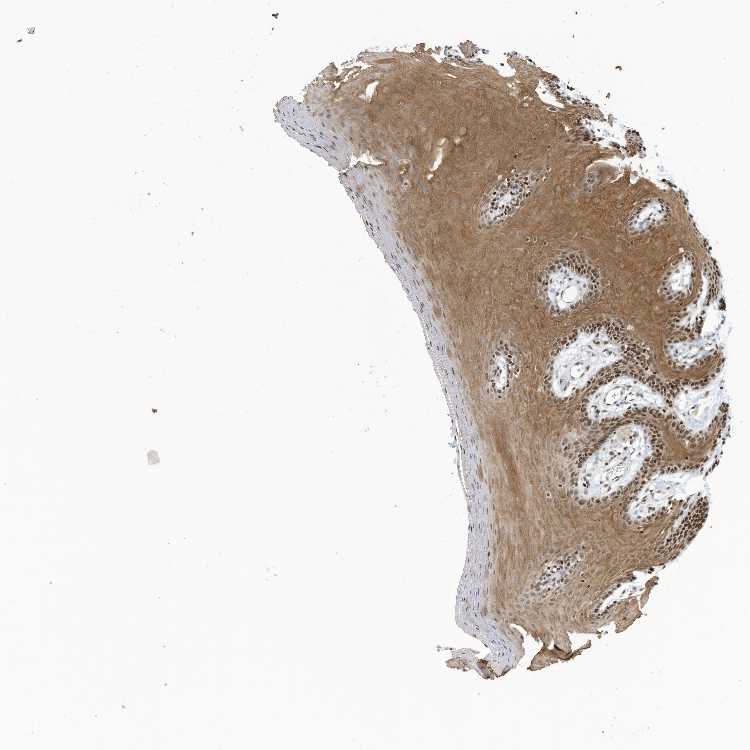

TISSUE PRIMARY DATA ORAL MUCOSA Show tissue menu

Oral mucosa

ORAL MUCOSA - Antibody stainingi

Antibody staining in the annotated cell types in the current human tissue is reported as not detected, low, medium, or high, based on conventional immunohistochemistry profiling in selected tissues. This score is based on the combination of the staining intensity and fraction of stained cells.

Each image is clickable and will lead to virtual microscopy that enables deeper exploration of all samples and also displays staining intensity scores, fraction scores and subcellular localization as well as patient and tissue information for each sample.

Antibody HPA035403Antibody HPA035404

Squamous epithelial cells MediumMedium